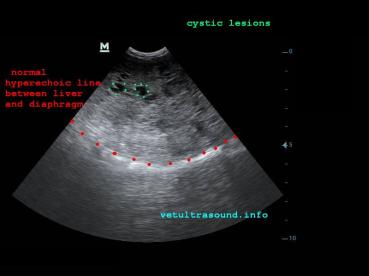

Στον υπέρηχο βρέθηκε ανομοιογένεια του ηπατικού παρεγχύματος, πολυάριθμοι κυστικοί σχηματισμοί οι οποίοι καταλάμβαναν κυρίως τον δεξιό πλάγιο λοβό του οργάνου(pic1&2). Η ροή του αίματος στη πυλαία φλέβα με τη βοήθεια του Pulse Wave Doppler βρέθηκε φυσιολογική(pic3), ενώ σε κλάδο της δεξιάς ηπατικής αρτηρίας ο δείκτης αγγειακής αντίστασης βρέθηκε μειωμένος(normal RI≈ 0.55)(pic4). Στοιχείο που μας δείχνει πως είτε η αγγείωση στη συγκεκριμένη περιοχή είναι νεόπλαστη, είτε λόγω χρόνιας νόσου ο διάμεσος ιστός που περιβάλλει τα αγγεία έχει χάσει την σκληρότητά του. Μικρή ποσότητα ασκιτικού υγρού βρέθηκε ανάμεσα στις εντερικές έλικες. Χωρίς παθολογικά διογκωμένους λεμφαδένες εκτιμήθηκε η κοιλιακή κοιλότητα(pic5). Οι υπόλοιπες δομές ελέγχθηκαν χωρίς παθολογικά ευρήματα.